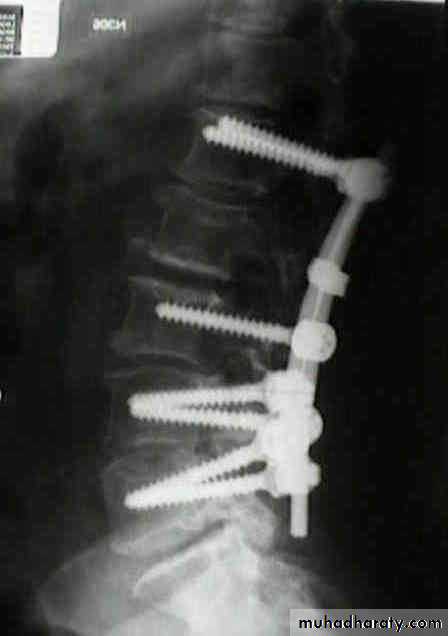

Treatment

It has been shown that persistent wedging of a vertebral body is compatible. With virtually normal function.

so correction of the deformity is not essential.

The standard method of treatment may, therefore, be said to be conservative.BURST FRACTURE OF A VERTEBRAL BODY

the compression force thus acts vertically in the line of the vertebral bodies.

The intervertebral disc is forced

In the affected vertebral body, causing a comminuted bursting fracture in which fragments are driven outwards in all directions.